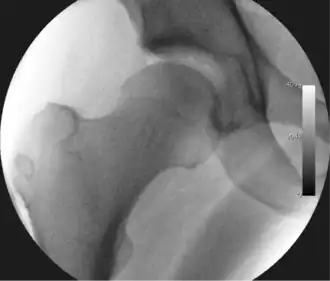

- Figure 3. Fluoroscopic picture showing a mild amount of distraction of the hip before insertion of any instruments

- Figure 4. A needle is passed into the joint, breaking the 'suction seal', and allowing further distraction of the hip joint with minimal extra traction

The procedure is performed with the patient asleep (general anaesthetic) or under spinal anaesthesia. There are two widely used methods, one with the patient on their back (supine) and the other on their side (lateral decubitus). Which is used is down to the surgeon's preference. To gain access to the central compartment of the hip joint (between the ball and socket), traction is applied to the affected leg after placing the foot into a special boot. (See fig. 2) There is specifically designed equipment for this, although some surgeons use a 'traction table', initially designed to help in the operative fixation of broken thigh and lower leg bones. The amount of traction (or pull) needed is assessed with the help of fluoroscopy (low-dose portable x-ray). (See fig. 3) It is usually not possible to distract the ball from the socket with traction alone by more than a few millimetres. Once the surgeon is happy that they will be able to gain access to the hip joint (i.e. the ball will distract from the socket by a small amount), the patient is then painted with antiseptic and the surgical drapes applied.

The next step is to insert a fine needle under x-ray guidance into the hip joint. This breaks the 'suction seal' of the joint and allows further distraction if necessary (see fig 4). The surgeon wishes to see the ball move out the socket by approximately 1 cm, so that access to the hip joint can be achieved with minimal risk of damage to the joint surfaces. Most surgeons will inject fluid into the joint at this stage, again to ensure that there is enough space between the ball and socket for safe instrument access. This needle is then removed. The next step is placement of the 'portals', or the small holes made to pass instruments into the joint. This is achieved by again passing a fresh hollow needle into the joint under x-ray control, usually in a slightly different position. The reason for this is so the surgeon can ensure that the needle, and subsequent cannulae do not penetrate and damage the acetabular labrum or cartilage joint surfaces (see fig. 5). Again, surgeons will have their own preferences as to their preferred placement. Through this hollow needle, a long thin flexible guide wire is passed into the joint, and the needle is removed over it, leaving the guide wire in situ. A small cut in the skin is made around the wire, to allow for larger cannulae to be placed over the wire through the portal. The wire therefore guides the larger cannulae into the joint. The most common external diameters of cannulae used are between 4.5 and 5.5 mm. Once the surgeon is satisfied that the cannula is in the correct position, by a combination of feel and x-ray guidance, the guide wire can be withdrawn. Once the first portal is correctly placed, any further portals may be created once the camera is in position, to ensure that they are placed with minimal risk to the joint surfaces. This process can be repeated to gain as many points of entry to the hip joint as the surgeon requires, normally between two and four. Certain of these entry points will be used for the viewing arthroscope and others for operating instruments.